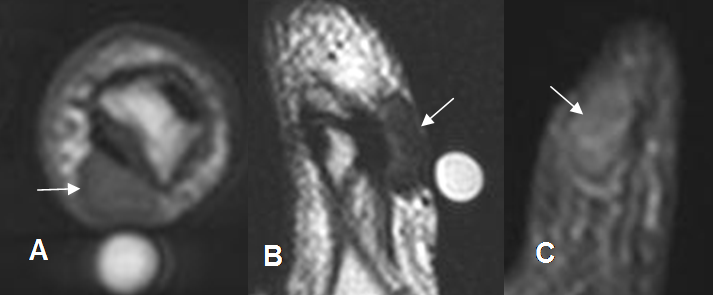

Fig 124 A. Tumor de células gigantes.

A: RM axial en T1, B: RM sagital en T2 y C: RM coronal en STIR. Tumor de células gigantes en la vaina tendinosa flexora del pulgar, manifestado por imagen ovalada y sólida, hipointensa en todas las secuencias.